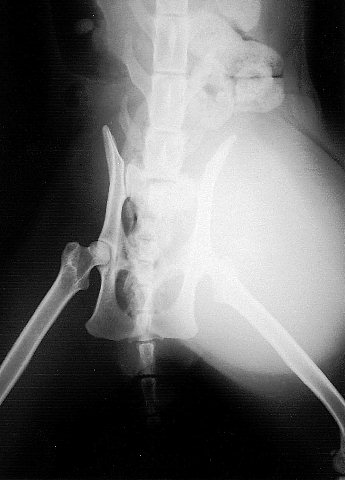

レントゲンではこのように写ります。

この症例では膀胱が入り込んでいました。